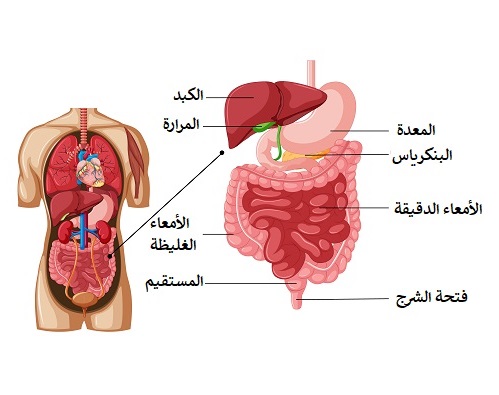

الأعضاء المساعدة في الجهاز الهضمي

الكبد

.الوصف: أكبر غدة في الجسم، يقع في الجانب الأيمن العلوي من البطن

الوظائف

.إنتاج العصارة الصفراوية التي تساعد في هضم الدهون-

.تخزين السكر على شكل جليكوجين وتنظيم مستوياته في الدم-

.إزالة السموم من الدم وتصنيع البروتينات المهمة لتجلط الدم-

البنكرياس

الوصف: غدة تقع خلف المعدة

الوظائف

:إفراز إنزيمات هاضمة مثل

.الأميلاز: لتفكيك النشويات

.الليباز: لهضم الدهون

.التريبسين: لتفكيك البروتينات

.إفراز هرمونات مثل الأنسولين والجلوكاجون لتنظيم مستويات السكر في الدم

المرارة

.الوصف: كيس صغير يقع تحت الكبد

الوظيفة

.تخزين العصارة الصفراوية التي ينتجها الكبد-

.إفراز العصارة إلى الاثنا عشر عند تناول الدهون لتسهيل هضمها-

يستعرض هذا الكتاب الجهاز الهضمي، أحد أهم أجهزة الجسم، الذي يحول الطعام إلى طاقة وعناصر غذائية ضرورية للحياة. يتناول الكتاب شرحًا لأعضائه الأساسية مثل الفم، المريء، المعدة، الأمعاء، والمستقيم، إضافة إلى الأعضاء المساعدة كالكبد، البنكرياس، والمرارة.